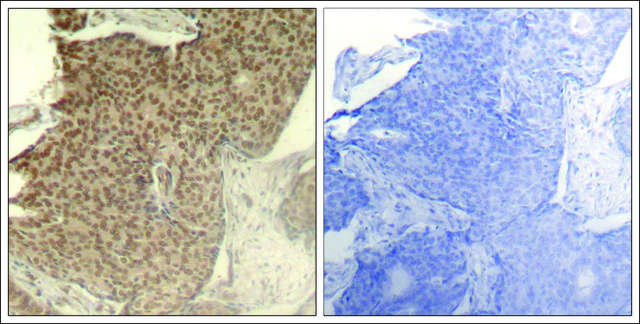

Anti-phospho-HDAC2 (pSer394) antibody produced in rabbit

翻译后修饰

物种反应

技术